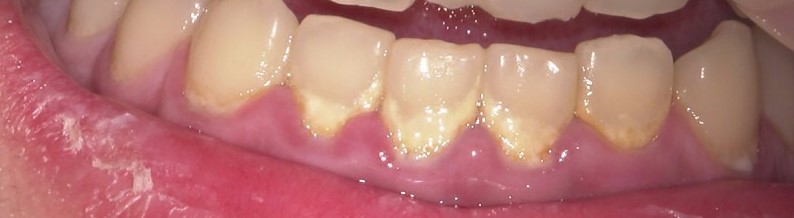

歯石除去はなかなか大変

歯石とは歯石(しせき) プラークが石灰化して硬くなったもの。 歯科医で定期的に除去することが必要。 不十分な歯磨きのため、プラークが長期間、歯の表面についているとき、唾液に含まれるカルシウムやリン酸がプラークに沈着して( […]